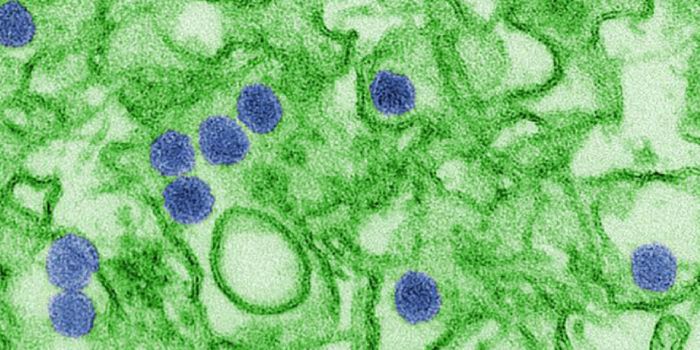

MAR 01, 2018Clinical & Molecular DXScientists found evidence of the yellow fever virus in urine and semen samples for almost one month after one São ...